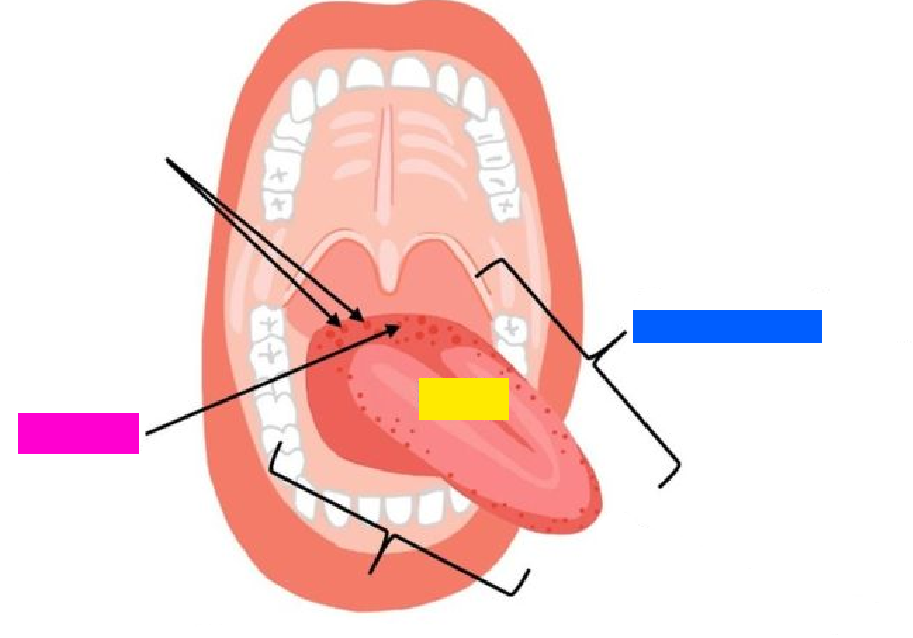

green highlight

Dorsum of tongue

blue box

Body of tongue

yellow box (referencing a section of the tongue)

Root of tongue

pink box

Papillae

(general term)

Lingual frenulum

Openings of submandibular ducts